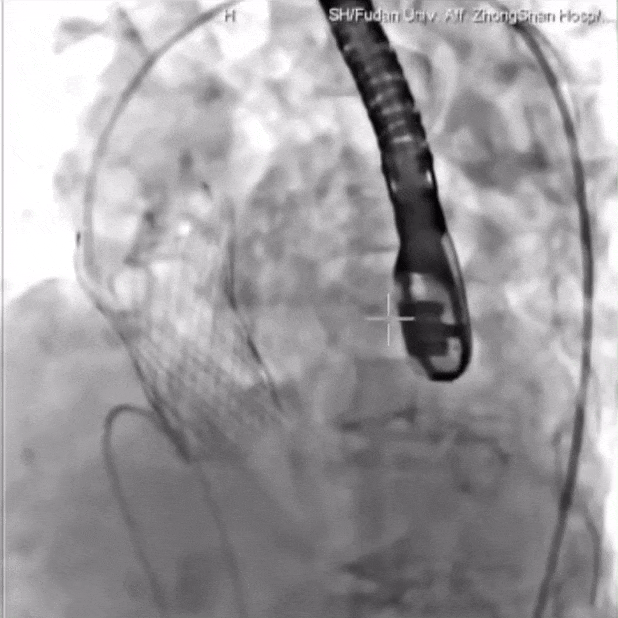

TaurusNXT植入过程:

瓣膜第一次展开与回收